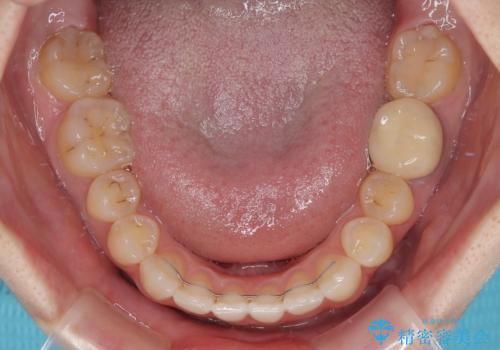

上顎骨を拡大することで、八重歯やデコボコを歯列に収めることができ、下顎の歯が外に位置していた奥歯の咬み合わせも改善することができました。

スペースも短期間に獲得できるため、1年程度で治療を終えることができました。